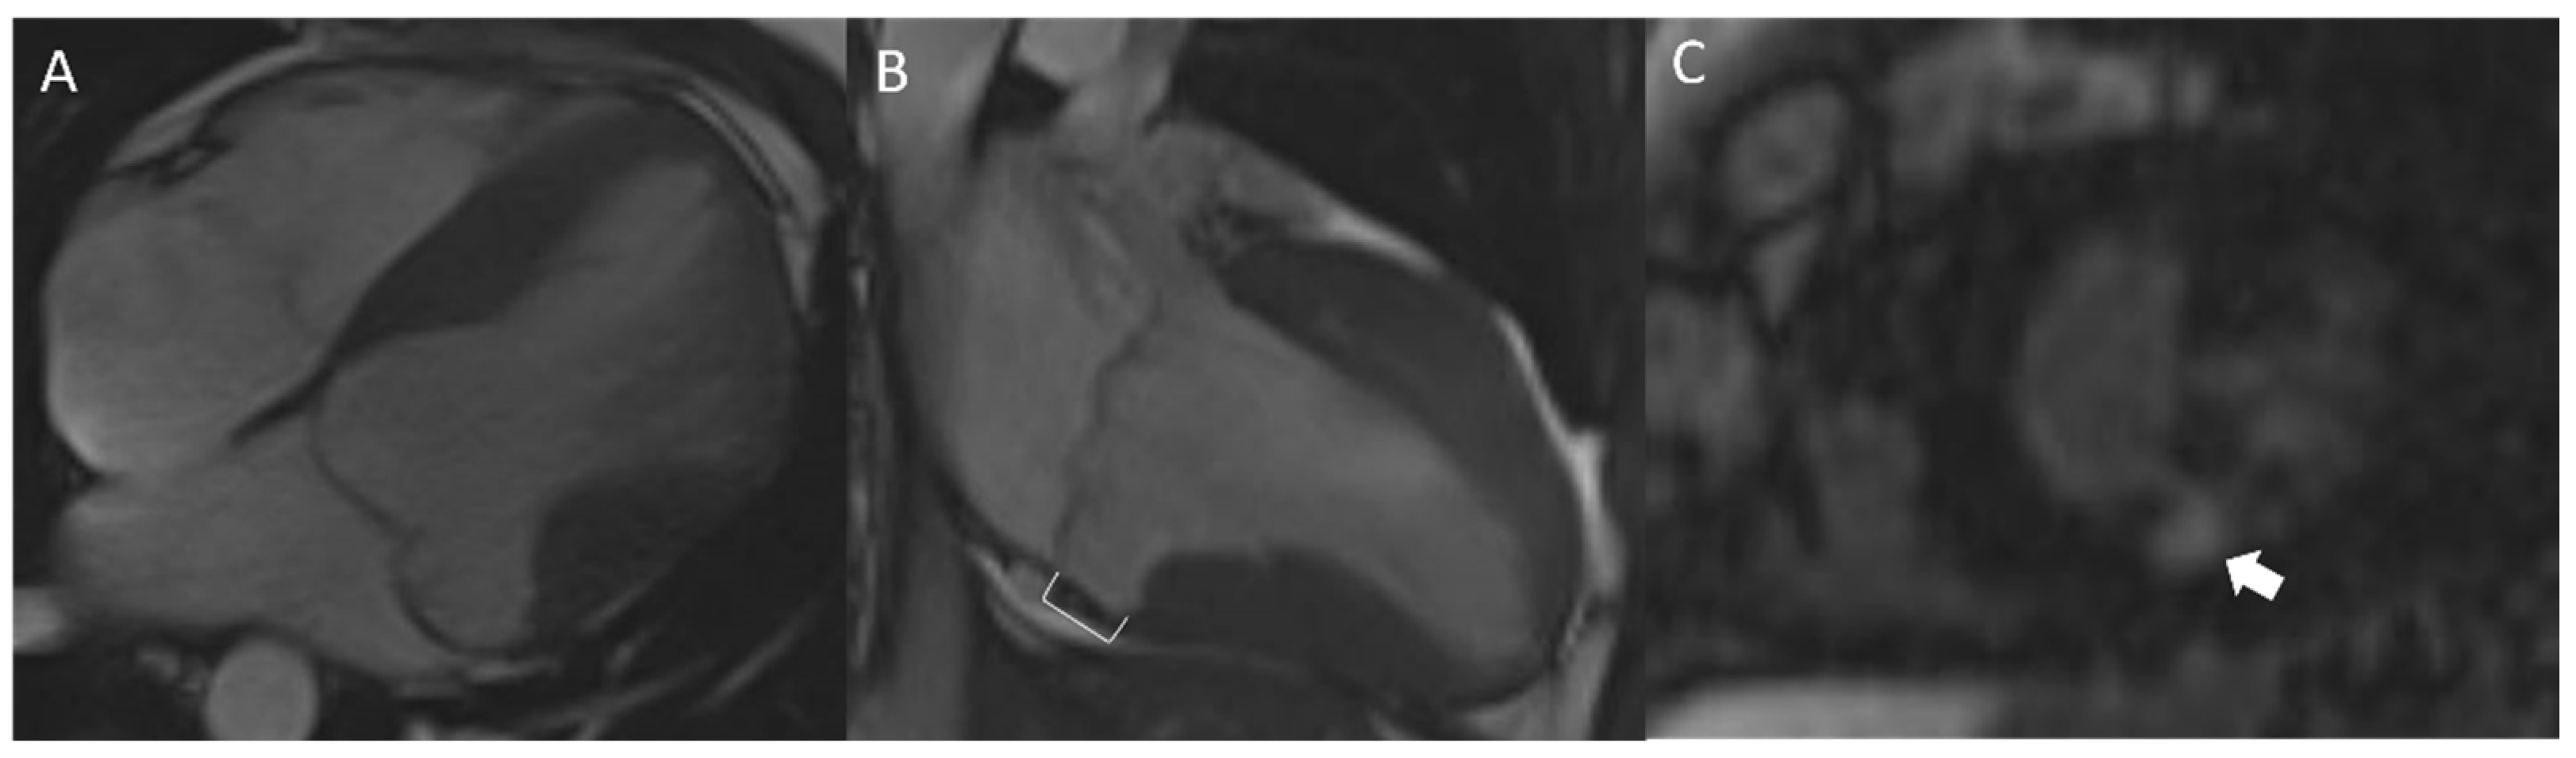

4.6. Cardiac Magnetic Resonance